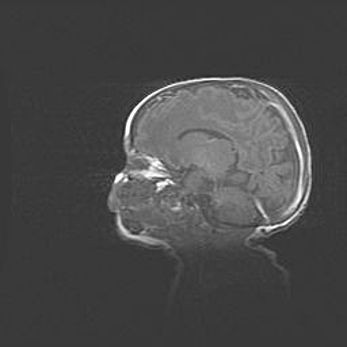

Неполная лизэнцефалия (пахигирия). Открытая гидроцефалия.

Возраст: 17 дней

Вес: 3110 г

Пол: мужской

Окружность головы: 33,5 см

Срок гестации: 35-36 недель

Лизэнцефалия—недоразвитие корковой пластинки и мозговых извилин в результате нарушения миграции нейронов коры. Поверхность мозговых полушарий гладкая. Микроскопически выявляется отсутствие нормальных слоев коры и скопление групп нейронов в подкорковом белом веществе.

Пахигирия—уменьшение числа вторичных извилин. В пораженном полушарии нервные клетки образуют толстый недифференцированный слой с неправильно расположенными нервными волокнами и группами гетеротопных клеток. Нервные клетки незрелые. Белое вещество истончено. При этом нередко аномально развит корково-спинномозговой путь.